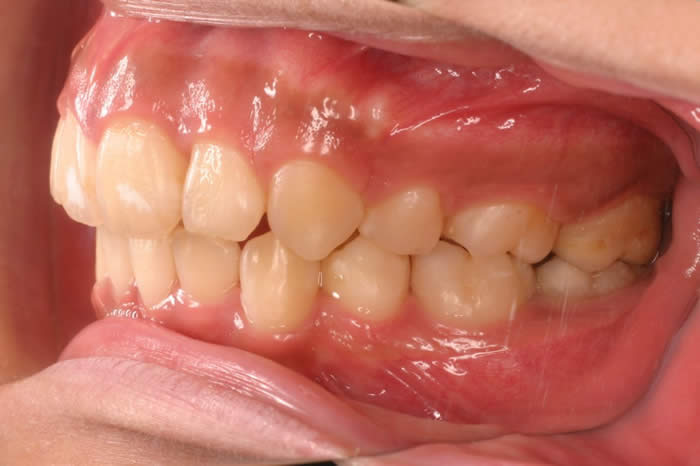

初診時右側面

初診時の口腔内写真です。重度の上顎前突症と叢生の合併症です。下顎をみると左側の第一小臼歯と右側側切歯が完全に歯列から逸脱し、上顎の前歯は下顎の前歯より1cm以上前突しています。

上顎両側の第一小臼歯と下顎両側の第一小臼歯を抜歯(合計4本)し、さらに、効果的に上顎前歯の後退をはかるため上顎口蓋側臼歯部に固定源のための歯科矯正用アンカースクリューを植立することにしました。